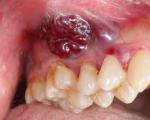

दो बच्चों के साथ 15 साल से मुंह के कैंसर को पाल रही आदिवासी महिला

दो बच्चों के साथ 15 साल से मुंह के कैंसर को पाल रही आदिवासी महिलाबालाघाट जिले के वनांचल क्षेत्रों में बसने वाली आदिवासी जनता अपनी दुर्दशा के अलावा कई घातक बीमारियों से भी जूझ रही है। जिले की बिरसा तहसील की मछुरदा पंचायत के अन्तर्गत आने वाले वन बाहुल्य ग्राम...